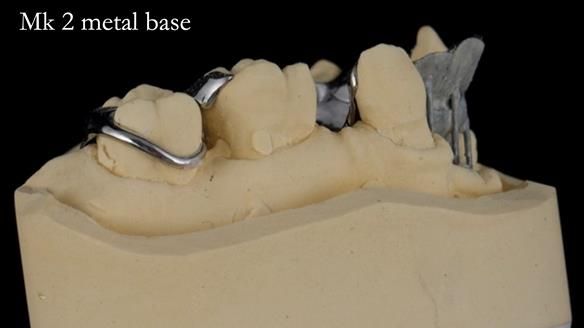

Jean’s Class I Mod III RPD: Learning from My Mistakes – From a Fractured Mk1 to a Stronger Mk2 (4 Years On)

In this edition, I present the removable partial denture treatment for Jean, an 80-year-old woman with a sore mouth caused by a soft tissue-supported 'gum stripper' acrylic denture and a clenching habit. Below, I outline the step-by-step process of her treatment. It wasn't straightforward; I had to remake the denture after it fractured to achieve a satisfactory result. Each patient is unique, and sometimes a new RPD serves as a prototype. Occasionally, I need to make adjustments, learn from any mistakes, and refine the design to get it right.

The treatment has been a success over the past 4 years.